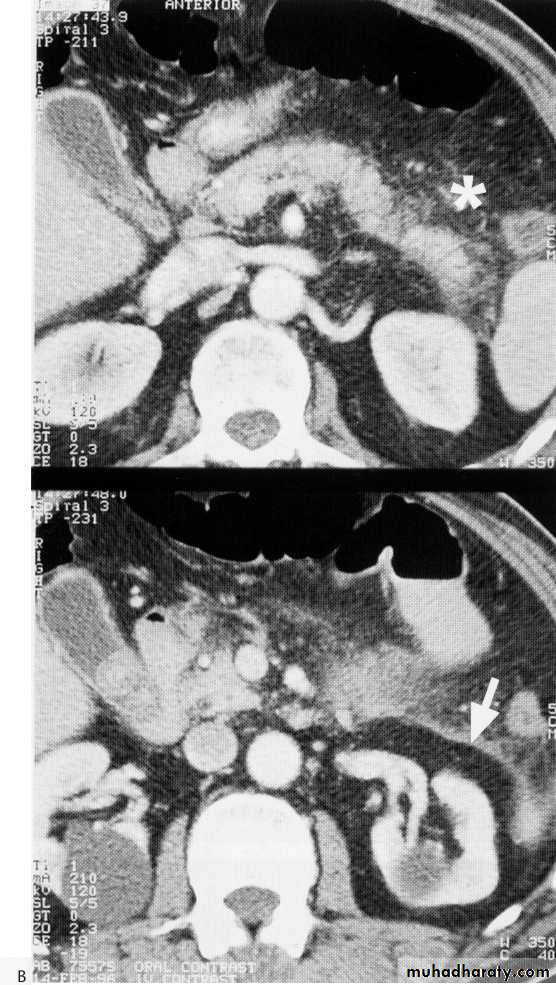

Ct scan carinal LAP

Advanced esophageal Ca